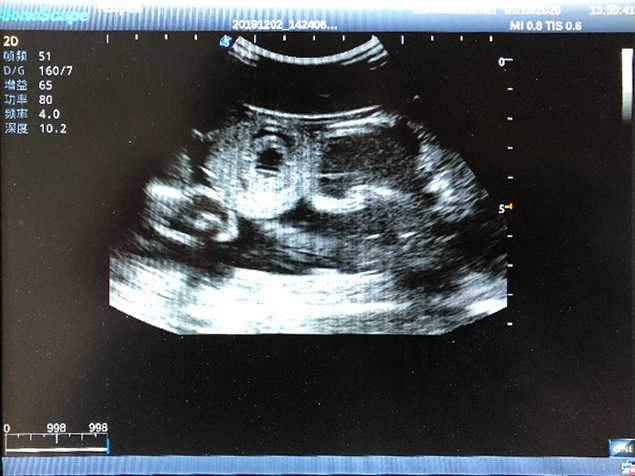

2) High quality ultrasound image with clear structures like gallbladder, liver, intestines, arteries and veins etc.

5) Normal & pathological ultrasound live and intestine models inside